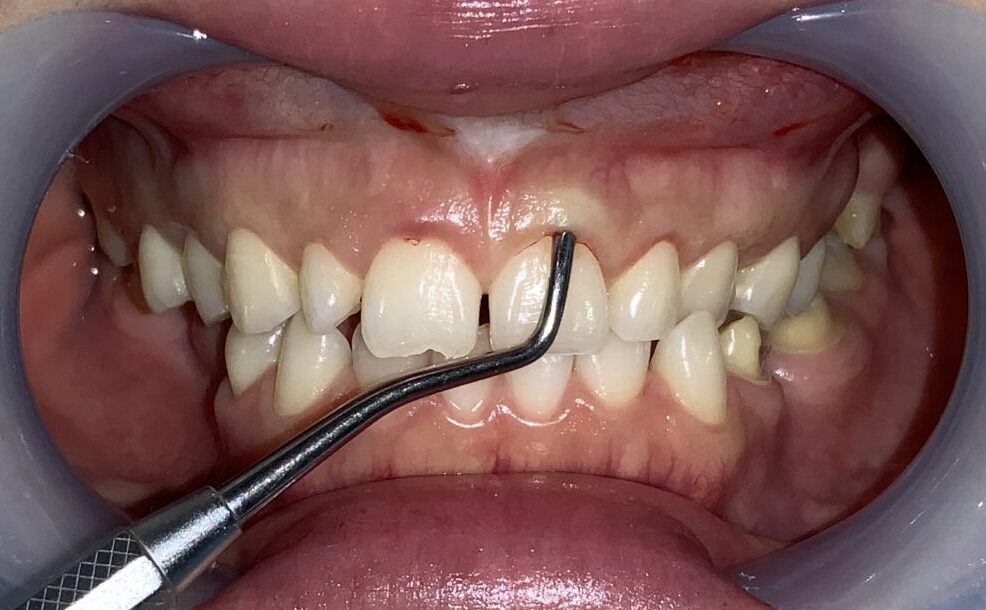

反対側の歯も同じように検査をしてみます。

歯に歯ぐきが大きくかぶっています。

歯ぐきを切り取る範囲を黒いマーキングペンでマーキングして、手術に挑みます。